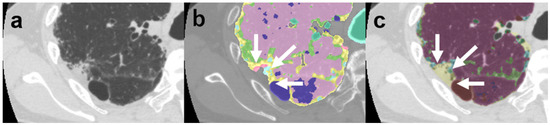

Review

Polymyositis and dermatomyositis are autoimmune idiopathic systemic inflammatory diseases, characterized by various degrees of muscle inflammation and typical cutaneous lesions—the latter found in dermatomyositis. The underlying pathogenesis is characterized by a high level of uncertainty, and recent studies suggest diseases may have different [...] Read more.

Polymyositis and dermatomyositis are autoimmune idiopathic systemic inflammatory diseases, characterized by various degrees of muscle inflammation and typical cutaneous lesions—the latter found in dermatomyositis. The underlying pathogenesis is characterized by a high level of uncertainty, and recent studies suggest diseases may have different immunopathological mechanisms. In polymyositis, components of the cellular immune system are involved, whereas in dermatomyositis, the pathogenesis is mainly mediated by the humoral immune response. The interstitial lung disease occurs in one-third of polymyositis and dermatomyositis patients associated with worse outcomes, showing an estimated excess mortality rate of around 40%. Lung involvement may also appear, such as a complication of muscle weakness, mainly represented by aspiration pneumonia or respiratory insufficiency. The clinical picture is characterized, in most cases, by progressive dyspnea and non-productive cough. In some cases, hemoptysis and chest pain are found. Onset can be acute, sub-acute, or chronic. Pulmonary involvement could be assessed by High Resolution Computed Tomography (HRCT), which may identify early manifestations of diseases. Moreover, Computed Tomography (CT) appearances can be highly variable depending on the positivity of myositis-specific autoantibodies. The most common pathological patterns include fibrotic and cellular nonspecific interstitial pneumonia or organizing pneumonia; major findings observed on HRCT images are represented by consolidations, ground-glass opacities, and reticulations. Other findings include honeycombing, subpleural bands, and traction bronchiectasis. In patients having Anti-ARS Abs, HRCT features may develop with consolidations, ground glass opacities (GGOs), and reticular opacities in the peripheral portions; nonspecific interstitial pneumonia or nonspecific interstitial pneumonia mixed with organizing pneumonia have been reported as the most frequently encountered patterns. In patients with anti-MDA5 Abs, mixed or unclassifiable patterns are frequently observed at imaging. HRCT is a sensitive method that allows one not only to identify disease, but also to monitor the effectiveness of treatment and detect disease progression and/or complications; however, radiological findings are not specific. Therefore, aim of this pictorial essay is to describe clinical and radiological features of interstitial lung diseases associated with polymyositis and dermatomyositis, emphasizing the concept that gold standard for diagnosis and classification–should be based on a multidisciplinary approach. Full article

Show Figures

Figure 1